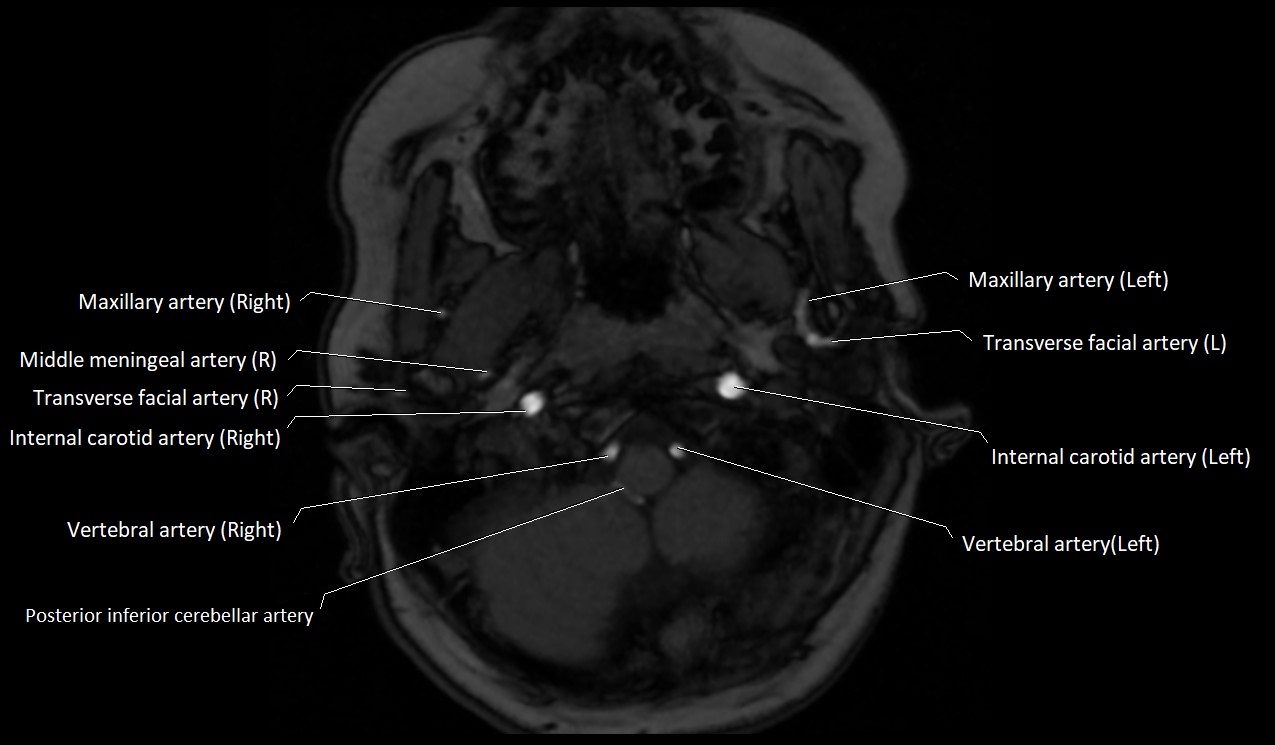

MRI images

image